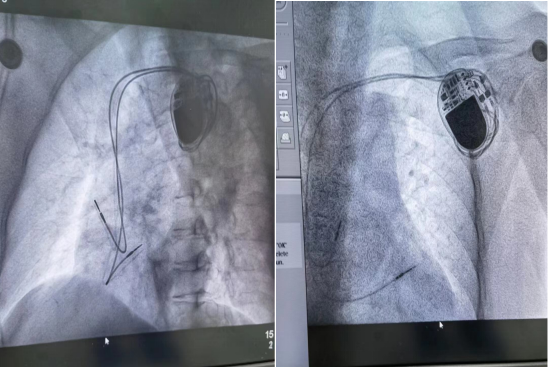

心脏起搏器安装术后造影图.png

本次手术由李勇主任主刀,主治医师黄生华协助,以及医护团队默契配合、细致操作,郭阿姨成功接受了在DSA下实施双腔永久性起搏器植入术。此例手术为我县首例,手术过程顺利,用时1小时30分钟,术后,起搏器工作正常,郭阿姨安返病房。术后第一天,心电监护提示窦性心律与起搏心律交替,郭阿姨感觉良好,无明显不适症状。术后一周如期拆线,切口愈合良好。在医护人员详细告知起搏器术后各项注意事项后,郭阿姨正常出院。